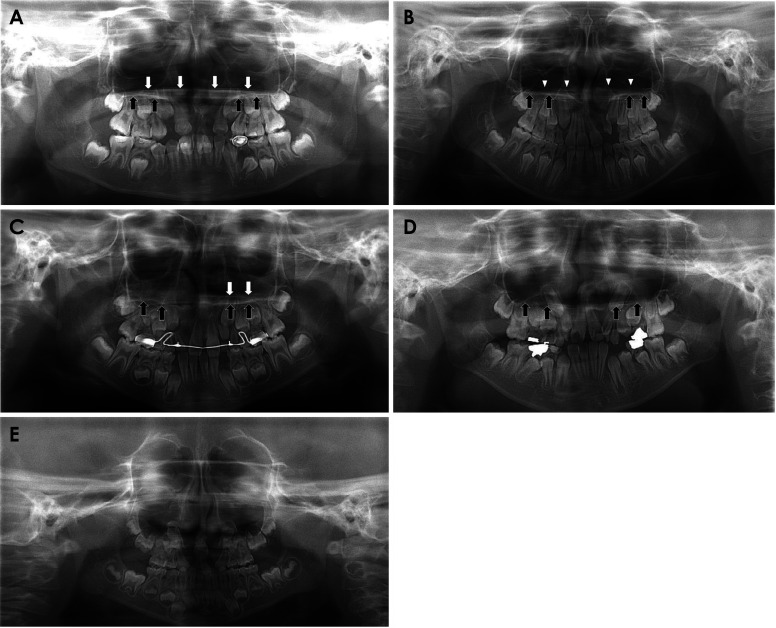

目的:本研究旨在明确有无腭裂的齿槽裂患者的全景图像差异,重点是鼻中隔和鼻底交界处形成的线(上线)的可见度以及上颌侧切牙的外观:对 238 名唇裂患者的全景照片进行分析,以了解上线的可见度(包括清晰、模糊或不可见)以及上颌侧切牙的外观(包括先天缺失、发育不全、萌出延迟和内倾)。结果显示,腭裂患者和非腭裂患者在这些可见度和外观的分布比例上存在差异:结果:腭裂患者和非腭裂患者的上线能见度分布存在明显差异(p):在全景图像中发现了两种差异。首先是腭裂患者的上线消失(不可见),其次是单侧腭裂患者患侧上颌侧切牙的内倾角发生变化。

Purpose: The purpose of this study was to clarify the panoramic image differences of cleft alveolus patients with or without a cleft palate, with emphases on the visibility of the line formed by the junction between the nasal septum and nasal floor (the upper line) and the appearances of the maxillary lateral incisor.

Materials and methods: Panoramic radiographs of 238 patients with cleft alveolus were analyzed for the visibility of the upper line, including clear, obscure or invisible, and the appearances of the maxillary lateral incisor, regarding congenital absence, incomplete growth, delayed eruption and medial inclination. Differences in the distribution ratio of these visibility and appearances were verified between the patients with and without a cleft palate using the chi-square test.

Results: There was a significant difference in the visibility distribution of the upper line between the patients with and without a cleft palate (p<0.05). In most of the patients with a cleft palate, the upper line was not observed. In the unilateral cleft alveolus patients, the medial inclination of the maxillary lateral incisor was more frequently observed in patients with a cleft palate than in patients without a cleft palate.

Conclusion: Two differences were identified in panoramic appearances. The first was the disappearance (invisible appearance) of the upper line in patients with a cleft palate, and the second was a change in the medial inclination on the affected side maxillary lateral incisor in unilateral cleft alveolus patients with a cleft palate.